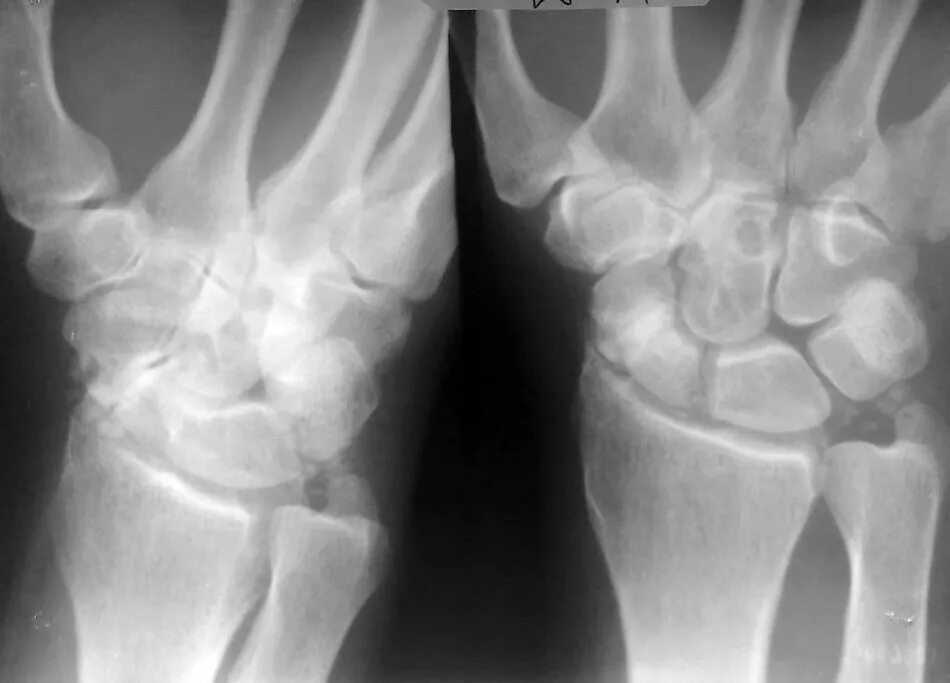

Перелом лучезапястного мкб